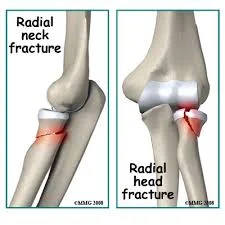

Fracture Radial Head / Neck

- Pain at elbow

- Localized swelling

- Inability to supinate/pronate. Might still be able to flex/extend elbow slightly

Fracture head

neck of radius